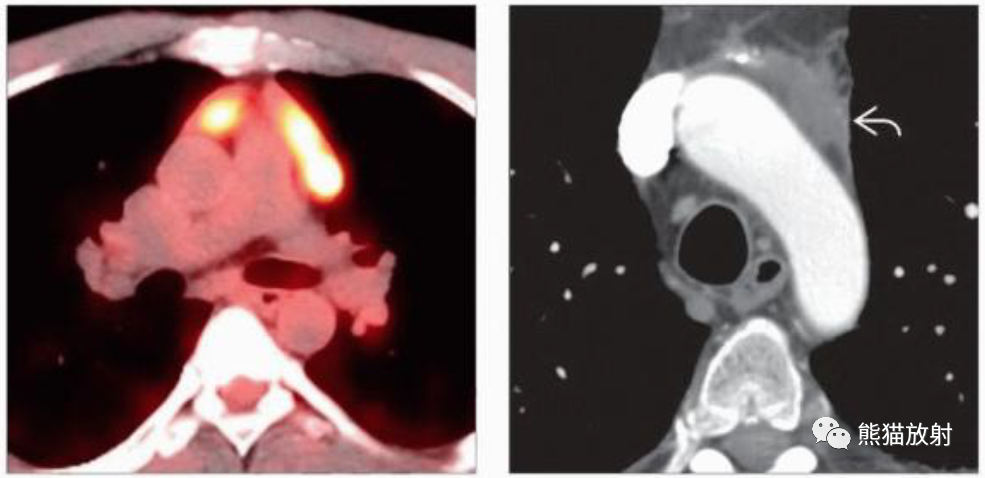

(左)39岁男性,偶然发现的前纵隔肿块轴位融合PET/CT显示FDG明显摄取。活检诊断为胸腺内精原细胞瘤。

(右)42岁男性,6cm大小的纵隔精原细胞瘤化疗4年后,CECT显示稳定的无强化的纵隔软组织密度灶。随访PET/CT未显示其有代谢活动。纵隔精原细胞瘤化疗或放疗后经常出现残留的软组织肿块。